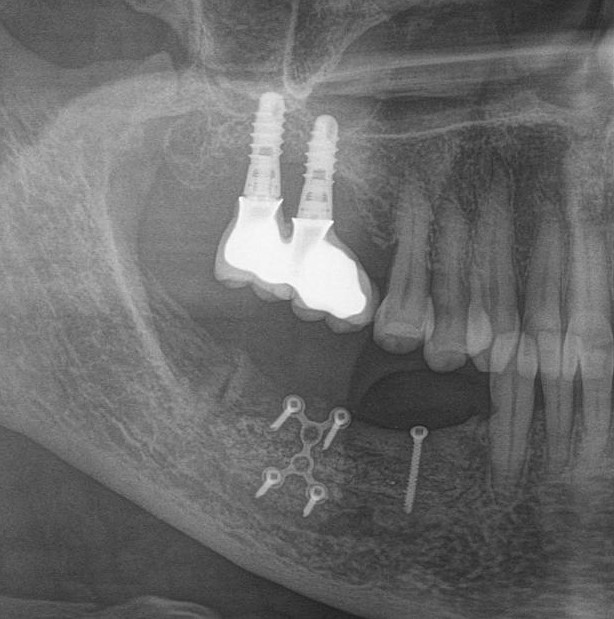

Тут представлена ошибка, как в позиционировании иплантата, так и в изготовлении вот такого великолепного мостовидного протеза.

Кроме уже известной нам цементной фиксации, с выведением материала под десну, меня добила форма этой конструкции. Она идеальна для того, чтобы под протез забивалась пища и хранилась там годами.

На самом деле, если бы был изготовлен мост адекватной формы, без нависающих краев, с хорошей промывной частью и винтовой фиксацией, то можно было бы избежать этой проблемы.

Но с другой стороны, если бы хирург правильно спозиционировал имплантаты, можно было бы изготовить коронки на каждый зуб по отдельности и не извращаться с мостовидным протезом. Это упрощает гигиену и уход за ортопедическими конструкциями.